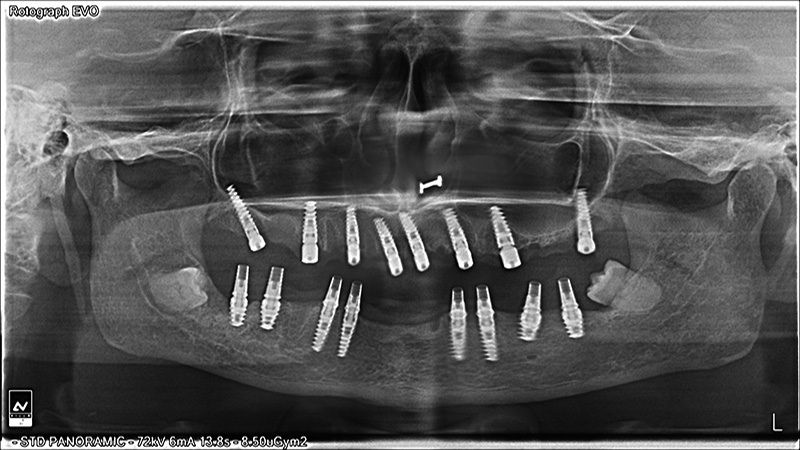

Implants

All on 4 Implants

All on 6 Implants

All on 8 Implants

FULL MOUTH REHABILITATION with IMPLANTS

Implant Patients